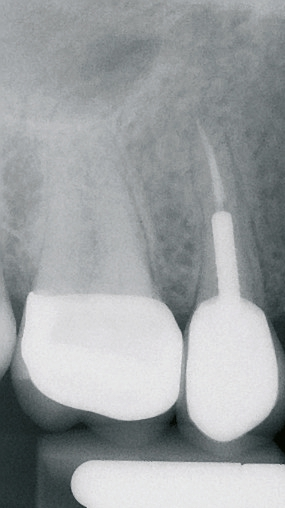

Um eine dreidimensionale Planung vornehmen zu können, wurde ein DVT erstellt und die Bilddaten wurden in die Planungssoftware 3Shape Implant Studio (3Shape, Kopenhagen, Dänemark) transferiert. Dort konnte die Implantation virtuell vorgenommen und in allen Raumdimensionen optimiert werden. Auf dieser Grundlage wurde eine Bohrschablone zur Teilnavigation hergestellt. Mittlerweile ist auch eine vollnavigierte, hülsenlose Implantation mit dem ceramic. implant möglich, das im Rahmen einer klinischen Studie eine noch präzisere Positionierung als bei den gängigen hülsengeführten Bohrschablonen zeigte [10].

Atraumatische Extraktion

In einem ersten Schritt wurde eine knochenschonende Zahnentfernung unter Erhalt der bukkalen Knochenlamelle mit dem Easy X-Trac System (Benco Dental, Pittston, Pennsylvania, USA) durchgeführt. Für einen Gewindestift mit Abzugshilfe wurde dabei ein Bohrloch im entsprechenden Durchmesser und in senkrechtem Einschub gesetzt. Mit einer Handratsche wurde der Stift lagestabil in den erweiterten Wurzelkanal eingedreht. Ein Löffel mit einer Öffnung für den Stiftkopf wurde nun einprobiert und anschließend mit Knetsilikon so individualisiert, dass eine schaukelfreie Abstützung auf den Nachbarzähnen gewährleistet war. An dem aus dem Abformlöffel herausragenden Stiftkopf wurde nun das Extraktionsinstrument angebracht, das eine rein vertikale Kraft auf den Stift und damit auf die verbliebene Zahnwurzel überträgt. Dadurch kommt es zu einer kontrollierten Ruptur der Sharpey’schen Fasern. Ohne traumatischen Hebeleinsatz auf Gewebe und Knochen konnte der Wurzelrest so am Stück entfernt werden.

Implantatinsertion

Nach sorgfältiger Kürettage und Inspektion einer idealen Knochenalveole vom Typ I [11] konnte mit der Sofortimplantation begonnen werden. Die ersten beiden Pilotbohrungen wurden teilnavigiert mit der Bohrschablone durchgeführt. Das restliche Bohrprotokoll wurde nach den Vorgaben des Herstellers frei durchgeführt. Mit der Insertion des Implantats konnte die nötige Primärstabilität von 35 Ncm für eine sofortige provisorische Versorgung erreicht werden. Im Vorfeld war ein Situationsmodell der Ausgangssituation und darauf eine Tiefziehschiene vorbereitet worden, die jetzt für die intraorale Herstellung des Provisoriums mit fließfähigem Kompositmaterial verwendet wurde. Als stabilisierende Gerüststruktur diente dabei die präzise sitzende Einbringkappe (insertion.transfer) auf dem Implantatkopf, die zuvor auf die entsprechende Höhe eingekürzt worden war. Nach der Ausarbeitung und okklusalen Adjustierung der Krone wurde diese provisorisch zementiert.